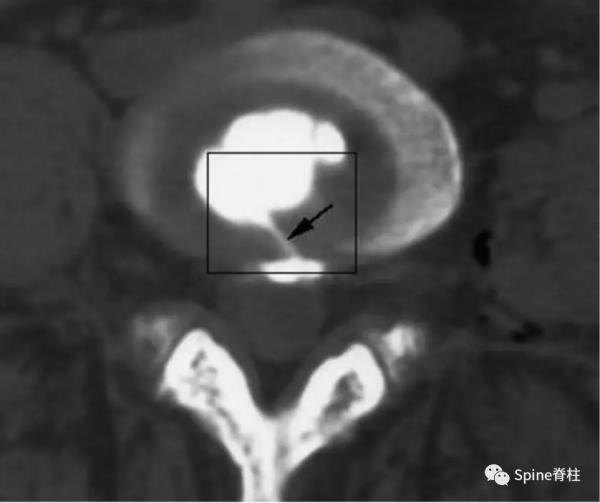

“黑椎間盤”是不是疼痛的?通常需要椎間盤造影或阻滯來明確或排除。雖有爭議,目前腰椎間盤造影術仍是診斷椎間盤源性腰痛的“金標準”。椎間盤造影誘發平時疼痛是明確疼痛椎間盤的有效方法,或者椎間盤內注射麻醉藥(比如布比卡因)後平時的腰痛症狀明顯消失。疼痛的椎間盤在造影劑注射過程中,造影劑要麼透過放射狀纖維環撕裂流向椎間盤外方,要麼透過放射狀終板撕裂流向椎體,兩者都誘發患者平時的腰痛反應。這也是鑑別終板源性腰痛和由纖維環撕裂引起的椎間盤源性腰痛的主要手段。

圖:椎間盤造影時,造影劑流至椎管

圖:椎間盤造影時,造影劑流至破損的終板